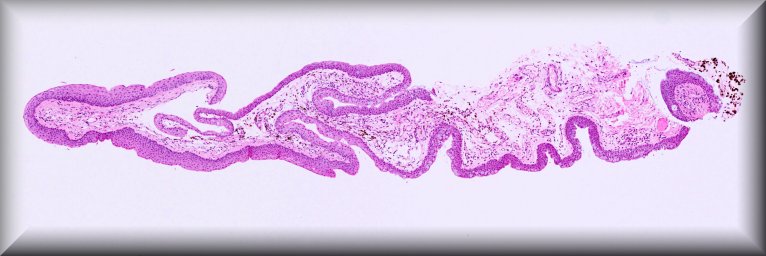

María Antonia Saornil (Valladolid): 19-year-old male patient who, in the last 3 months, had a progressive and extensive protrusion in the temporal sclera of the left eye. The patient also reports noticing loss of nasal visual field. |